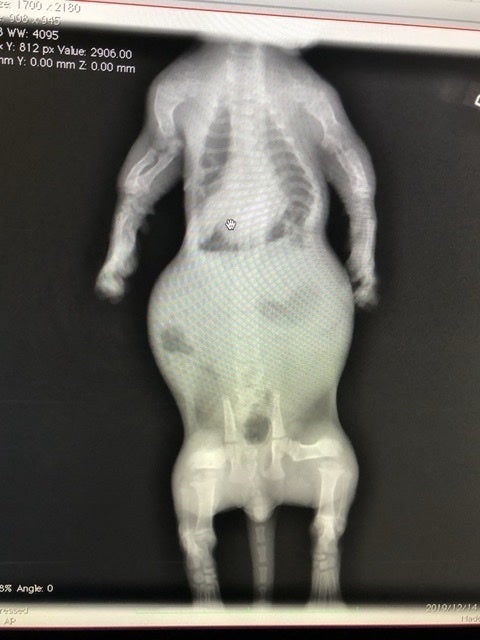

肋骨変形に伴う脊椎側変症

先天的な骨格異常で背骨と肋骨が変形していると診断されました。

また、この骨格異常により、肋骨と背骨の間のスペースが狭く、このまま成長していくと心臓と肺が圧迫され最悪生きられないと言われました。

レントゲン、CT撮影で費用が嵩む上、成長過程のため、複数回必要とのこと。これらを総合し、合計150万円〜は用意しておいて下さいと言われました。